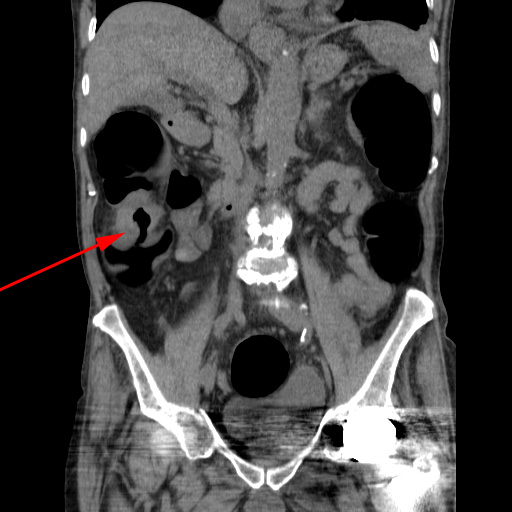

CT-kolografi (koronal rekonstruktion) der viser tumor i colon ascendens (rød pil).